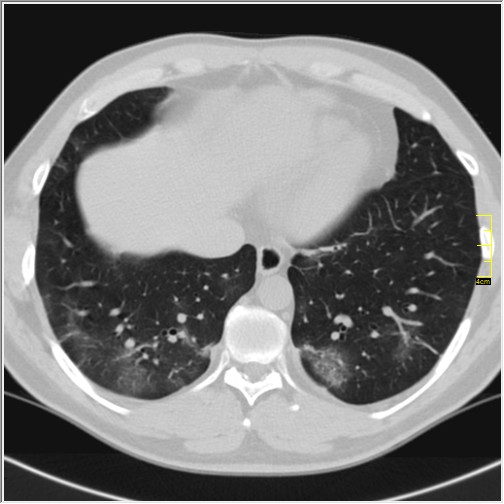

Kako sam radiolog moja nauka se izražava kroz slike. Ovo su pacijenti pregledani samo u jednom danu, godišta od 1991. do 1999.

Kao što sam rekao, slike govore sve. Ono što se razlikuje od ranijih pacijenata je obavezna hilarna limfadenopatija i gustina ground glass promena već u prvoj fazi. Ono što mi kliničari kažu je da ide sa visokom temperaturom, čak i preko 40 i da su svi simptomi izraženiji, sem gubitka čula mirisa i ukusa, koje je retko.